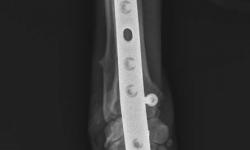

Pacient č. 3. - pooperační rtg, stav po osmi měsících.

Pacient č. 3. - pooperační rtg 2., stav po osmi měsících.